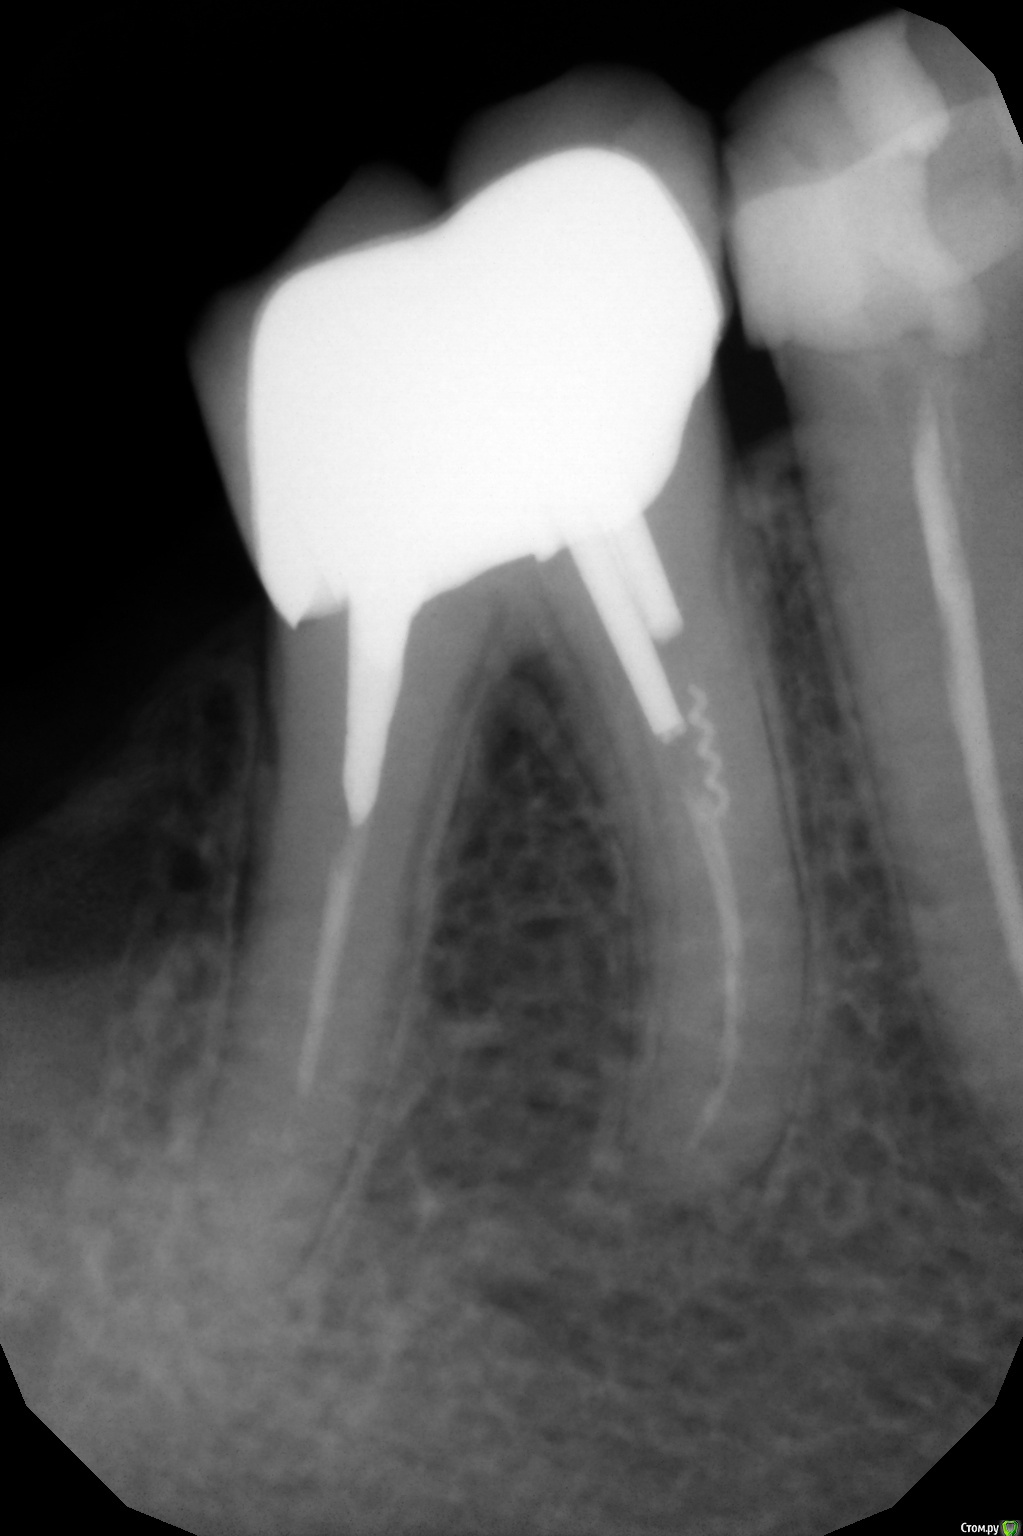

Musya31 Опубликовано 14 августа, 2017 Автор Поделиться Опубликовано 14 августа, 2017 Прикрепляю снимок Ссылка на комментарий

dok1 Опубликовано 14 августа, 2017 Поделиться Опубликовано 14 августа, 2017 Перелечивание даст эффект, если каналы пройдут до верхушек. В одном канале сломан инструмент. Ищите врача. В любом случае попытку сделать надо. Ссылка на комментарий

dok1 Опубликовано 15 августа, 2017 Поделиться Опубликовано 15 августа, 2017 Если извлеч инструмент и роойти каналы, то великолепные прогнозы. 1 Ссылка на комментарий